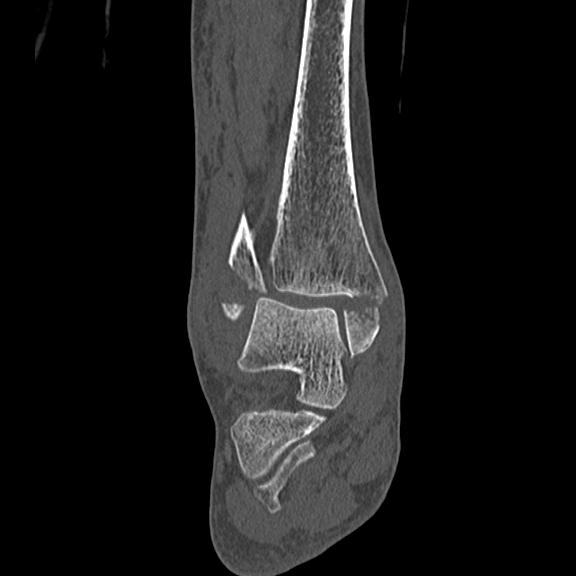

102755 1/4 2R 1/15 2R 右足関節 68歳女性 右三果脱臼骨折